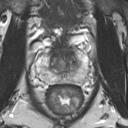

We present a novel technique to discover and exploit weak causal signals directly from images via neural networks for classification purposes. This way, we model how the presence of a feature in one part of the image affects the appearance of another feature in a different part of the image. Our method consists of a convolutional neural network backbone and a causality-factors extractor module, which computes weights to enhance each feature map according to its causal influence in the scene. We developed different architecture variants and empirically evaluated all of our models on two public datasets of prostate MRI images and breast histopathology slides for cancer diagnosis. To confirm our quantitative results, we conduct ablation studies and investigate the explainability of our models via class activation maps. Our findings show that our lightweight block extracts meaningful information and improves the overall classification, together with producing more robust predictions that focus on relevant parts of the image. That is crucial in medical imaging, where accurate and reliable classifications are essential for effective diagnosis and treatment planning.